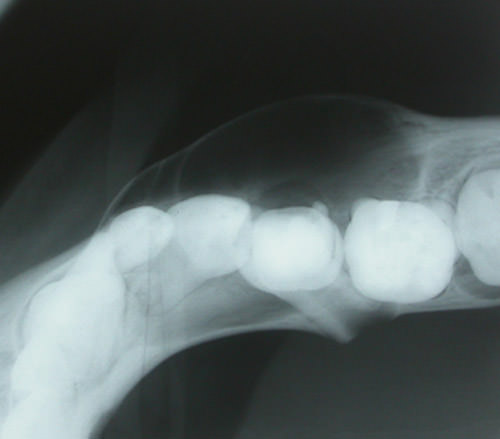

Paciente del sexo masculino de 9 años de edad, sano, sin antecedentes mórbidos de importancia. Fue derivado a la unidad de cirugía maxilofacial por un aumento de volumen en la zona mandibular derecha de aproximadamente 2 cm de diámetro. Presentaba expansión delimitada de la tabla vestibular de consistencia dura. Asintomática y de evolución indeterminada. Al examen intrabucal el diente 8.5 (Segundo molar temporal inferior derecho) presentaba una obturación extensa. La radiografía reveló una zona radiolúcida unilocular de límites netos en relación al premolar. El diente 8.5 presentaba tratamiento endodóntico y rizalisis (Figura 1) y en la radiografía oclusal se observa la expansión de la cortical ósea vestibular. (Figura 2).

Radiografía retroalveolar diente 8.5 con obturación extensa y reabsorción radicular avanzada. Se aprecia lesión radiolúcida delimitada asociada a diente 4.5 incluida.